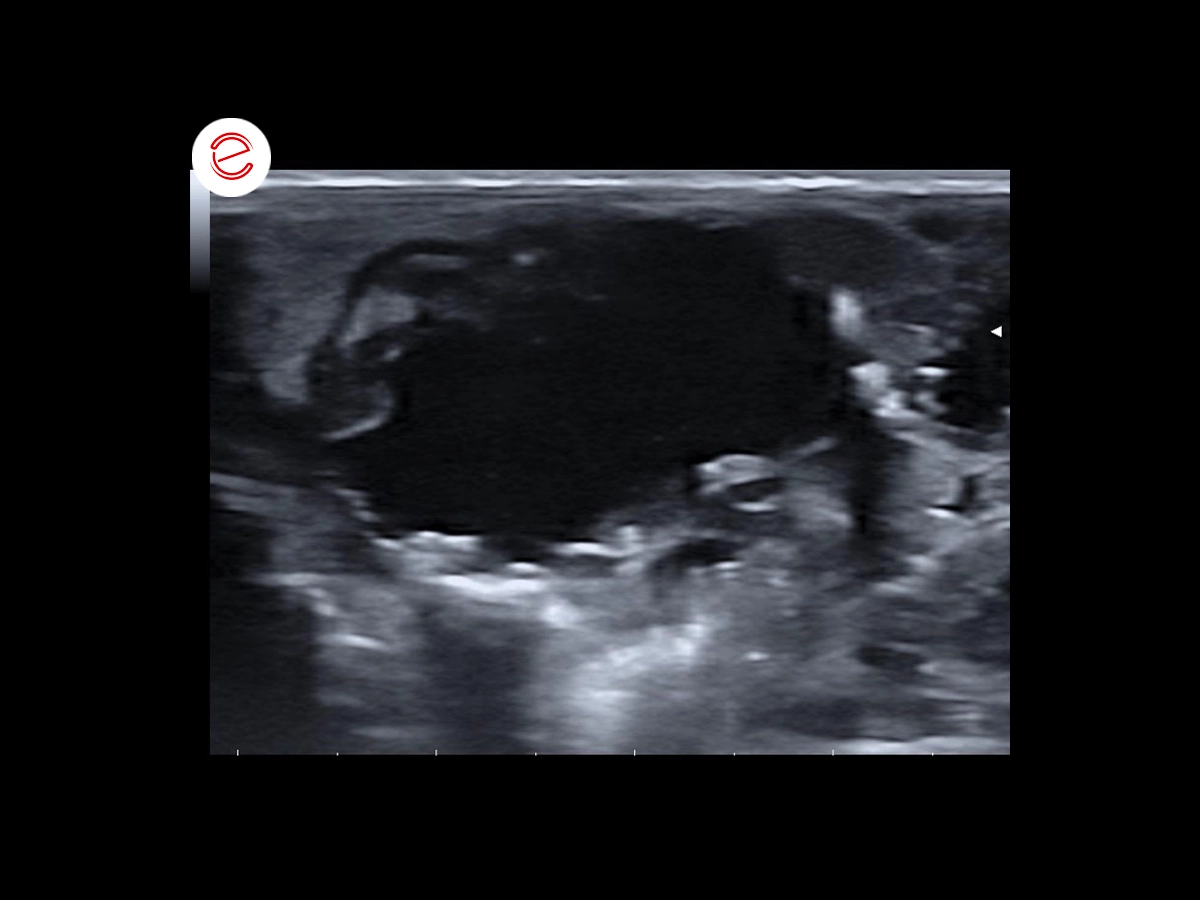

Distended gallbladder, thickened and irregular wall, showing mobile echogenic sediment in the slopes and hyperechogenic punctures with some posterior acoustic shadowing.

Images were acquired using the MyLab™Omega VET system.

The changes observed in the gallbladder were extremely suggestive of cholangitis with associated stasis/delay in biliary emptying. Neoplastic etiology was less likely but couldn´t be categorically ruled out.